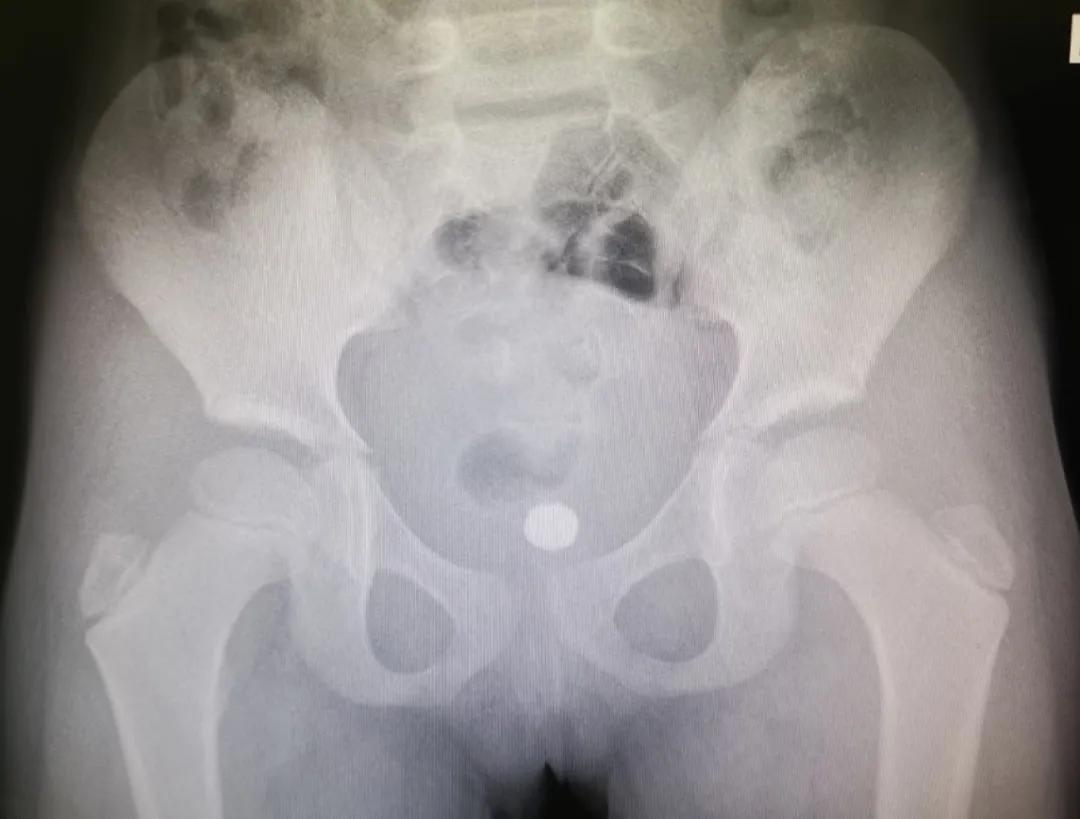

11岁男孩一个多月前,因好奇将12颗磁力珠从尿道塞入。12颗磁力珠在膀胱内紧紧相连,并吸附尿垢,形成一个中间带坚硬“结石”的较大环状异物。最终只能开放下膀胱切开取出异物。

10岁男孩2年前从尿道口塞入了一段长约7-8米的钓鱼线。日积月累下里面充分了结石,形成一个大团块。最终也只能开放下膀胱切开膀胱取出异物。